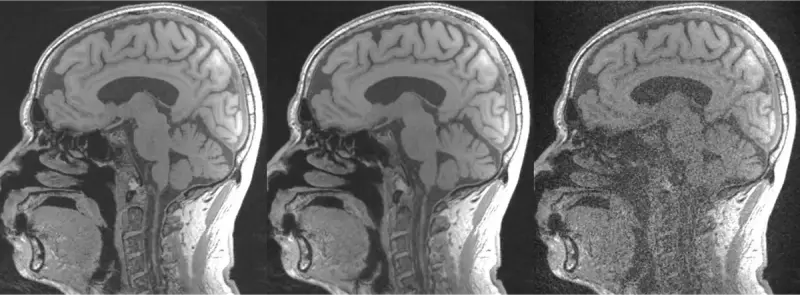

2019년, Facebook AI Research(FAIR)와 NYU Langone Health는 AI를 통해 MRI 스캔 속도를 최대 10배까지 향상시키기 위해 제1회 fastMRI 챌린지를 개최했습니다. 이 대회의 일환으로 NYU 랭곤 헬스는 완전히 익명화된 원시 데이터와 17,000개 이상의 MRI 이미지 데이터 세트를 공개하여 MRI 연구의 광범위한 머신러닝 커뮤니티에서 ML의 임상적 채택을 가속화했습니다.

서울대학교 공과대학이 2020 FAIR-NYU fastMRI 챌린지 우승자가 설립한 의료 AI 스타트업인 AIRS Medical과 함께 매년 캠퍼스 전체에서 주최하는 서울대학교(SNU) fastMRI 챌린지가 이 이니셔티브를 이어가고 있습니다. 이 대회는 매년 30개 이상의 분야에서 150개 이상의 팀이 모여 ML 가속 MRI 이미징의 최신 트렌드를 탐구하고 실제 임상 데이터와 챌린지 전용의 강력한 GPU 리소스로 최첨단 재구성 모델을 구축합니다.

MRI 재구성은 GPU와 데이터 집약적인 작업입니다. 예를 들어, AIRS Medical의 2020 fastMRI 챌린지 우승 모델은 7일 동안 4개의 NVIDIA V100에서 2억 개 이상의 파라미터를 훈련했습니다. 서울대학교는 이를 150배로 확장하여 150개 이상의 팀이 각각 자체 모델을 훈련하고 최적화할 수 있는 환경을 구축하고자 했습니다.

학교의 머신러닝 인프라에 쉽게 액세스할 수 있고 VESSL의 가이드 워크플로우를 통해 SOTA 모델 실험의 장벽이 낮아져 CS 배경 지식이 없는 학생들도 빠르게 AI 강화 연구와 애플리케이션을 시도할 수 있게 되었습니다. 이를 통해 연구자들은 MRI 스캔에 AI를 사용하는 것과 같이 이전에는 불가능했던 학제 간 가능성을 탐구할 수 있게 되었습니다.